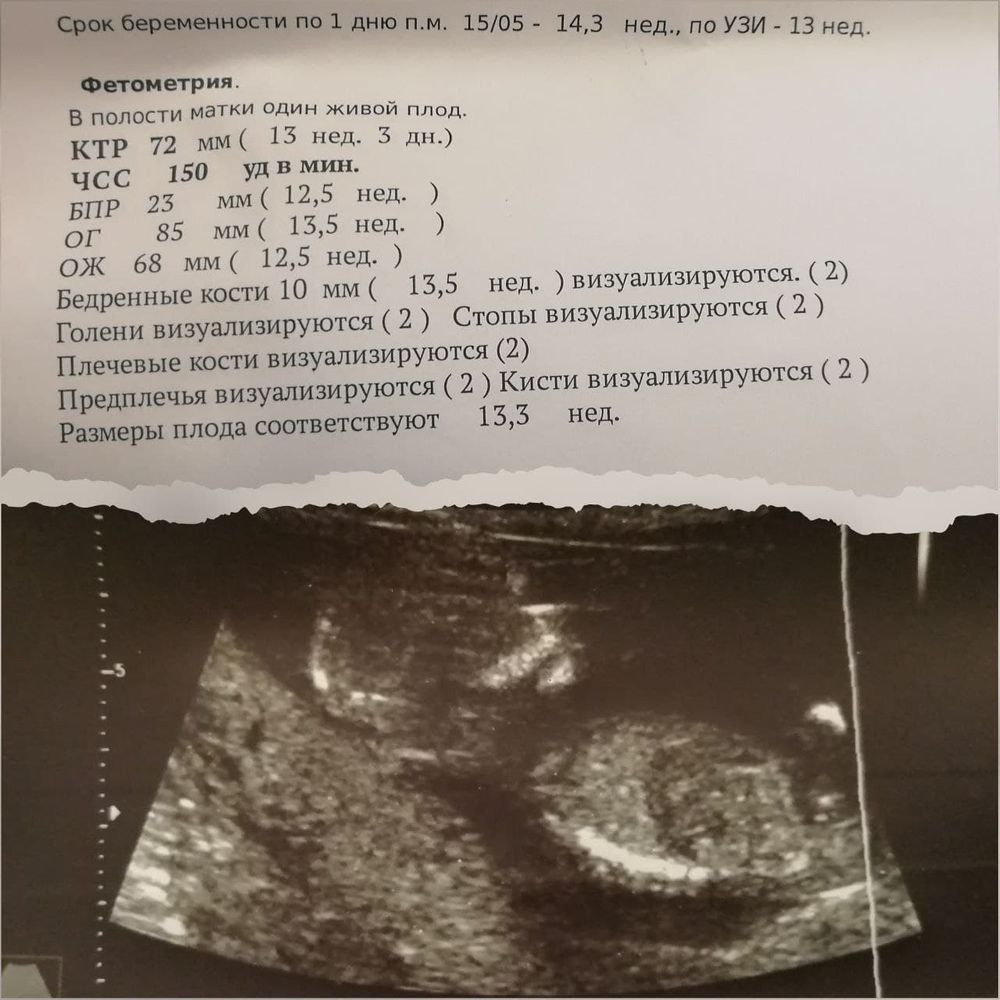

Первый скрининг и конец 1 триместра ⭐

Изображение

Ура! Наконец то я дождалась своего многострадального скрининга! У малыша все отлично. Врач все УЗИ хвалила сердце и сосуды. Минут 20 я лежала, пока врач пыталась посмотреть каждую деталь. Сначала